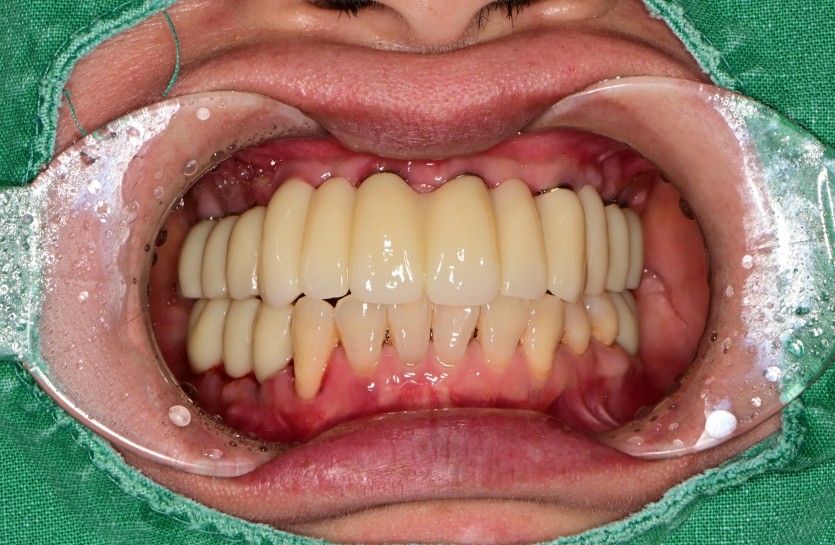

만 52세 상악 전체 임플란트 증례(하악 일부)

상악 전체 임플란트 증례입니다.(하악 일부)

14개의 임플란트로 완성하였습니다.